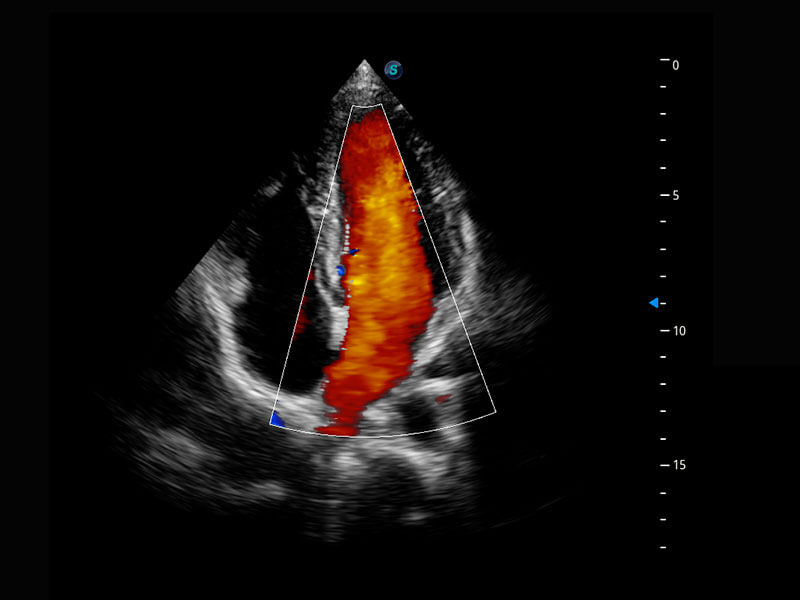

P60搭载宽频带线阵探头、宽景成像、弹性成像技术,为您提供乳腺应用方案。P60支持高频相控阵探头、线阵探头、腹部高频探头、腹部微凸探头等,丰富的探头群搭载敏感的彩色血流成像,适用于新生儿多种脏器检测要求,满足新生儿筛查需求。

乳腺导管癌

乳腺癌显微血流

新生儿肝血管癌

新生儿脊髓圆锥

新生儿心脏